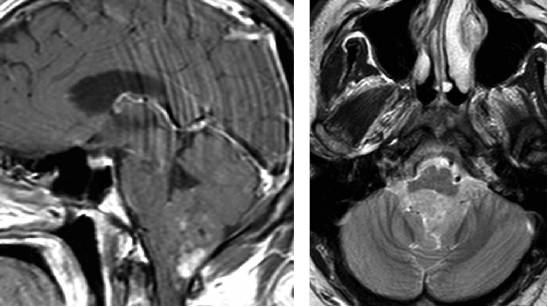

图3. 图示为向四脑室延伸和压迫的蚓部毛细胞星形细胞胶质瘤。肿瘤呈囊性,伴有明显强化的结节。囊壁未见强化,无需手术切除。